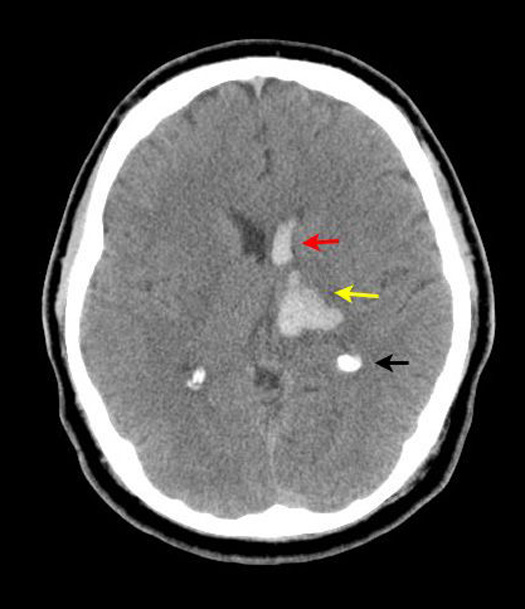

Figure 2: Non-contrast axial CT head

Hypertensive Hemorrhagic Infarct

Case 2:

Imaging findings: Figure 2

-

Hemorrhage (hyperdense area) involving left basal ganglia/thalamic regions (yellow arrow) is noted.

Extension of hemorrhage into left frontal horn (red arrow).

Black arrow points to normal calcification of choroid plexus.

Hemorrhage secondary to hypertension is more common in basal ganglia / thalamic regions.

Not a candidate for thrombolytic therapy or anticoagulation. |